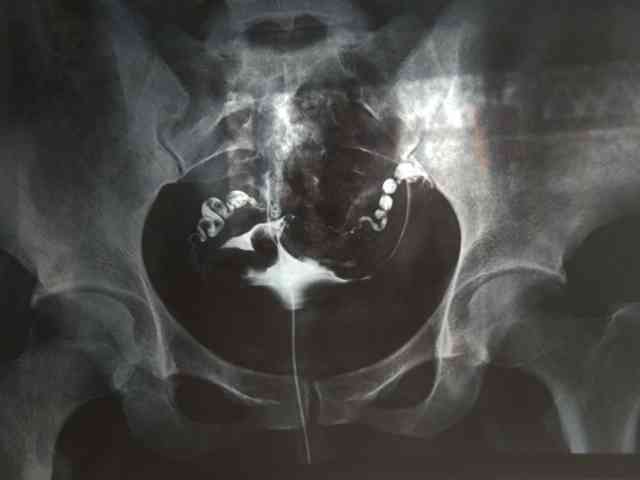

輸卵管堵塞患者通常無明顯症狀,部分患者可能出現下腹部疼痛、經量異常、發熱等症狀。嚴重時,可能引起白帶增多、全身無力、不孕、異位妊娠等併發症。一般而言,輸卵管堵塞很難通過自查診斷。患者應及時前往醫院就診。輸卵管可以說是女性很重要的生殖器官,在很多朋友知道在不孕症患者當中因為輸卵管因素無法懷孕的情況大約佔到三分之一以上,這樣一個比例,讓很多備孕不懷孕的朋友擔心自己可能就是因為輸卵管問題而無法懷孕。其中輸卵管堵塞是最主要的一個因素,所以說對於很多的女性來說要學會自己檢查輸卵管是否堵塞,這樣可以更好的懷孕。

輸卵管堵塞4個自查方法分別是看自己是否白帶增多、月經紊亂、經常性會出現腹痛、痛經嚴重,這幾點是臨床上面所總結的,建議姐妹們可以進行參考。